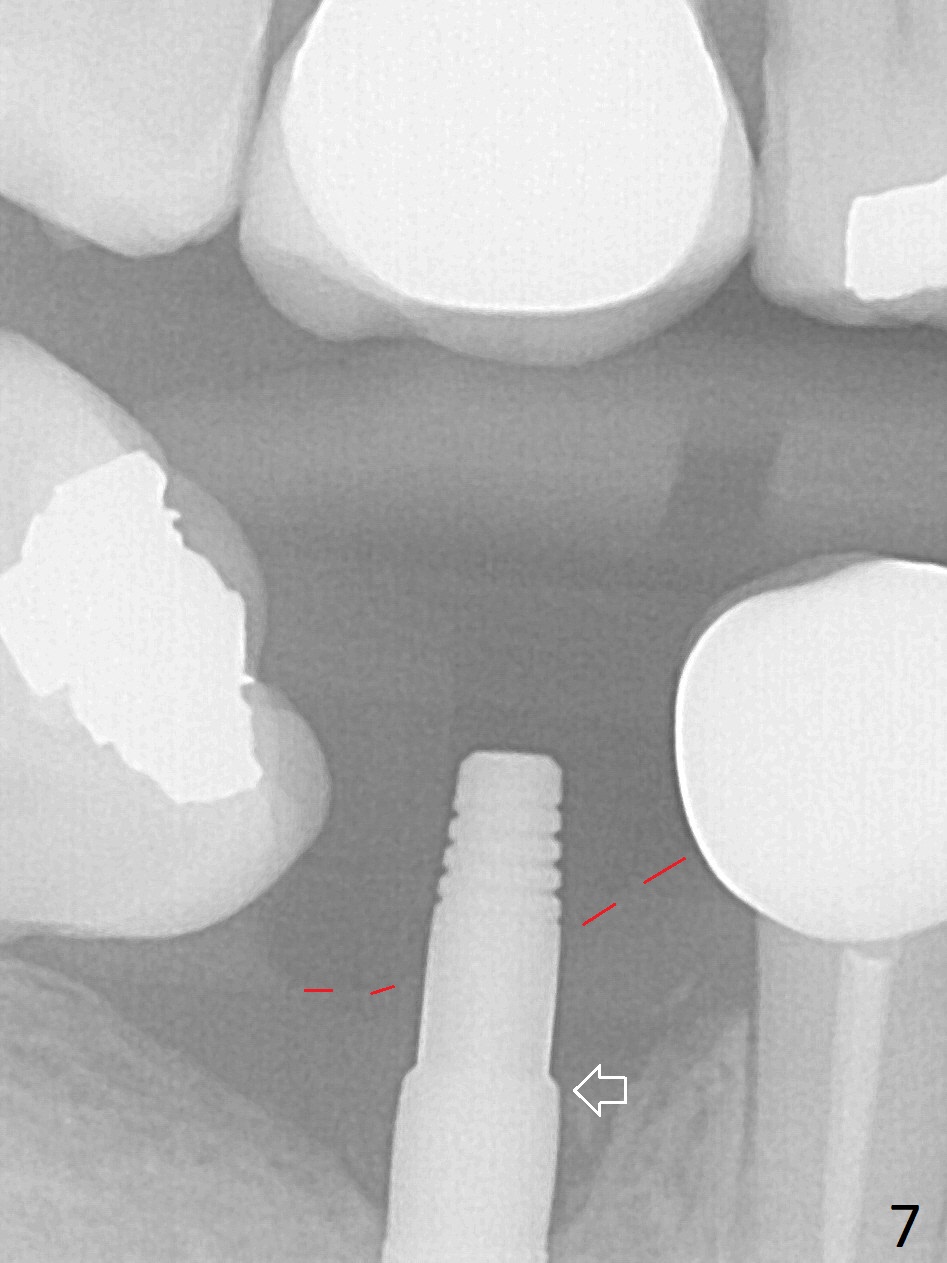

Incision reveals a narrow ridge and a narrow mesiodistal space at #30 (Fig.1). It seems that a 1-piece implant is indicated. Due to limited mouth opening, a 1.2 mm drill is unstable in place after use for 10 mm; instead a 1.5 mm drill is able to be inserted for 8 mm (Fig.2). A 3x10(2) mm 1-piece dummy implant is placed with 40 Ncm at an apparently acceptable level (Fig.3 >). Clinically a few threads are exposed buccally. When a definitive implant with the same dimension is inserted with 45 Ncm, it looks seated too deep (Fig.4,5). The latter is noted after suturing. The implant is backed up for a few turns so that the length of the abutment appears a little more reasonable. Introspectively, a 4 mm cuff should have been used after ridge reduction. Although there is no bone loss 4 months postop (Fig.6), the abutment margin (Fig.7 arrow) is subgingival (red dashed line: gingival margin). Diode laser is used for gingivectomy prior to impression. The bone density around the implant increases 11 months post cementation (Fig.8 *), probably related to recurrent #18 infection. The patient uses floss after meal.